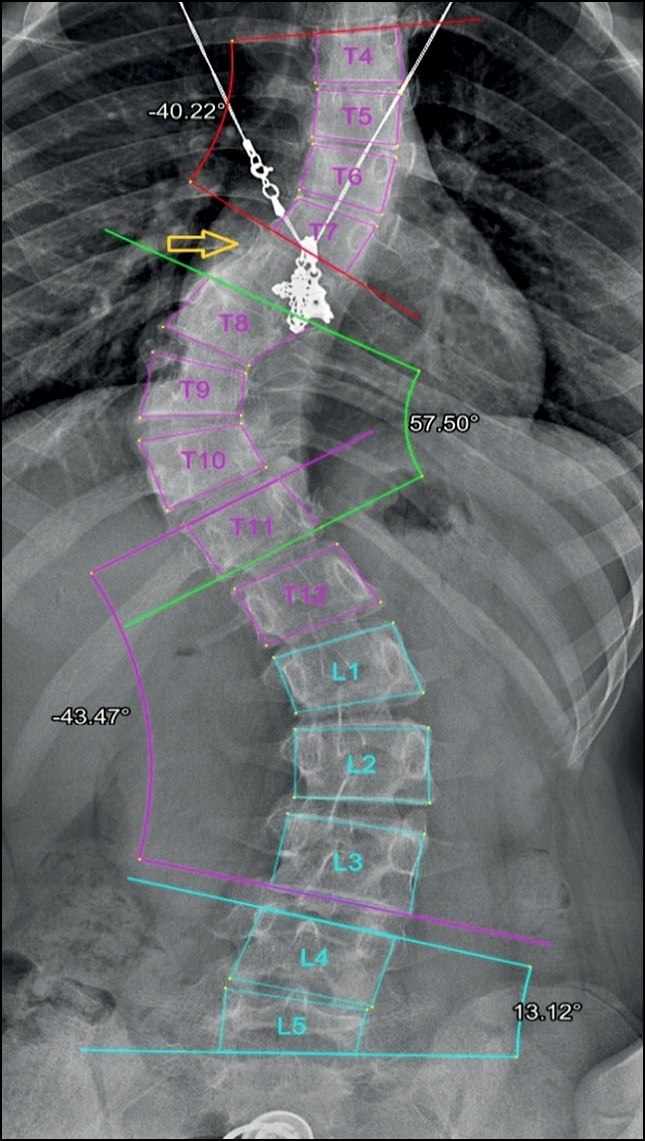

In addition, in most cases, the system accurately evaluated radiographs with severe scoliosis (grades III and IV), although errors in vertebral detection and numbering or errors in measuring Cobb’s angle sometimes were noted. Grade IV scoliosis is characterized by maximum vertebral rotation, with displacement of the pedicle beyond the midline and deformation of the vertebral body. Thus, the usual shape of the vertebra changes, and the edges of its body become less defined (Fig. 9).

Fig. 9. Specifications of vertebral marking in radiographs with grade 3 and 4 scoliosis. Errors in detection and numbering of vertebrae caused by the unusual shape of the vertebrae (yellow arrow).

In some cases, the accuracy of the system in diagnosing grade III or IV scoliosis was not affected by significant measurement variability of Cobb’s angle between the system and the radiologist. Usually, these errors had been mainly found when assessing a nonprimary (secondary) curvature (Fig. 10).

Fig. 10. Grade 3 scoliosis diagnosed by the radiologist (left) and the AI system (right). Significant variability in measuring the lumbar curve (7.8°) did not affect the overall scoliosis grade.